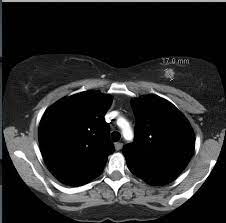

Can Chest Ct Scan Detect Breast Cancer - Chest Xray Xray Image Woman Chest Stock Photo Edit Now 1588387525 / A chest ct scan can detect even smaller nodules in the lung.. A ct scan may be done to: Computed tomography scan, ct scan, cat scan, and spiral or helical ct a ct scan can help doctors find cancer and show things like a tumor's shape and size. Learn the stage of your cancer. 95% of nodules found are benign. The scan is painless and takes about 10 to 30 minutes.

Once a nodule is found, a workup is done to see if it is cancer. Right now, ct scans aren't routinely used to look for breast cancer, but may be used to look at chest, spine, or abdominal problems, such as a herniated disc or lung disease. Nuclear imaging makes images by detecting radiation from different parts of the body after a radioactive tracer material is injected or taken by mouth. If you have a large breast cancer, your doctor may order a ct scan to assess whether or not the cancer has moved into the chest wall. Sandy,i asked my onc.he says ct's can pick up breast cancer depending part on location.i guess it's like real estate,location,location,location,lol.but seriously theradiologist who read my lung ct in november wrote in his report specifically there was no evidence of breast cancer.i guess due to them watching a lymph gland for 2 years on my rt breast.it was fine in mammogram in october so i am now back to yearly,thank god,andib Ct scans of the chest are used to find lung nodules or other chest pathology. Since then she has spent two weeks in hisputal with a chest infection, collapsed lung and aspiration problems. The term tomography comes from the greek words tomos (a cut, a slice, or a section) and graphein (to write or record). Computed tomography scan, ct scan, cat scan, and spiral or helical ct a ct scan can help doctors find cancer and show things like a tumor's shape and size. By comparing ct scans done over time, doctors can see how a tumor is responding to treatment or find out if the cancer has come back after treatment. Computed tomography scan, ct scan, cat scan, and spiral or helical ct a ct scan can help doctors find cancer and show things like a tumor's shape and size. 234 views answered >2 years ago A total body ct scan generally includes at least the chest, abdomen, and pelvis.

Follow Up Of Patients With Breast Cancer Imaging Of Local Recurrence And Distant Metastases Springerlink from media.springernature.com Doctors often use this is for cancer staging. Computed tomography scan, ct scan, cat scan, and spiral or helical ct a ct scan can help doctors find cancer and show things like a tumor's shape and size. Ct scans can help doctors: Areas commonly scanned for cancer include the head, neck, chest, abdomen, pelvis, or limbs. The value of preoperative staging chest computed tomography to detect asymptomatic lung and liver metastasis in patients with primary breast carcinoma. Cas article google scholar 6. A ct scan can help detect a wide range of abnormalities or disease, including cancer, in any part of the body. Scans give doctors the ability to diagnose lung cancer in the earliest stages, which allows for a better cure rate.